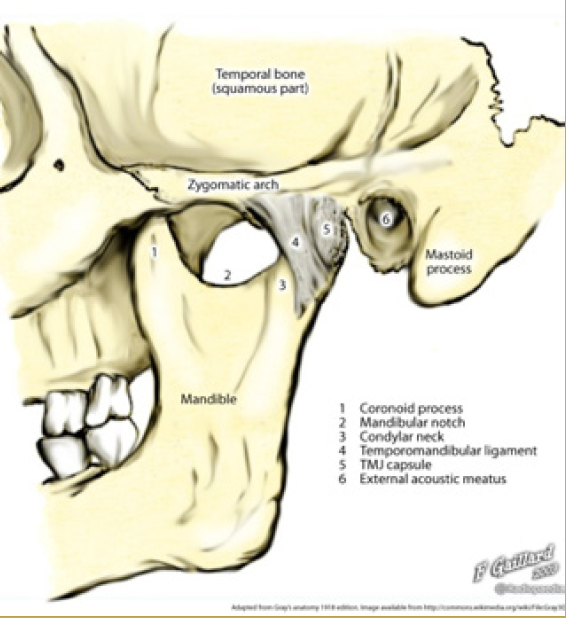

Fractures of the Bone

Fractures of the facial bones present an even more complex problem. The most frequent site of bony injury is the zygoma (cheekbone). Fractures of the zygoma account for approximately 10% of the maxillofacial fractures seen in sports injuries, occurring as a result of direct blunt trauma from a fall, elbow, or fist.12 In a study by Linn and others, of the 319 patients treated for sports-related injuries, males proved to be more prone to zygomatic fractures than females because of the powerful physical contacts during sports.13 Like the zygoma, the prominent shape and projection of the mandible cause it to frequently be traumatized. Approximately 10% of maxillofacial fractures from sporting activities occur in the mandible when the athlete strikes a hard surface, another player, or equipment. In a mandibular fracture, airway management is the most important aspect of immediate care.14 In both children and adults, the condyle is the most vulnerable part of the mandible. Fractures in this region have the potential for long-term facial deformity. Recent data suggest that condylar fractures in children can alter growth of the lower face.11

Fig 1. TMJ Landmarks

Figure 1